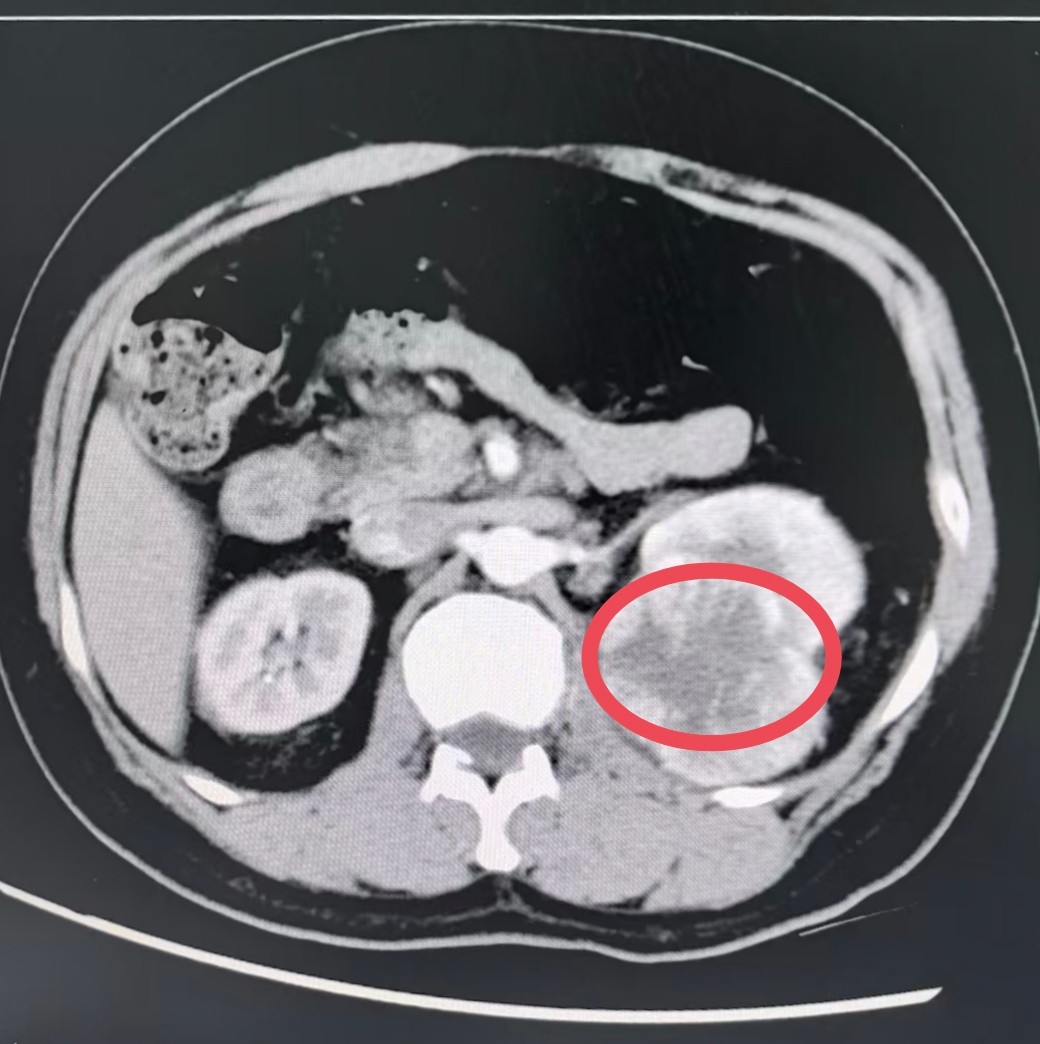

而就在不久前,一个直径达7.5*5.5厘米的肿瘤,正悄然藏在他的左肾上极,如同一个危险的“地雷”。

因左侧腰腹部持续隐痛并出现血尿,黄先生在当地医院就诊,查出左肾肿瘤,初步诊断为肾癌。若采用传统开放手术,需切开一道15至20厘米的创口,创伤大、出血多,康复之路漫长。为寻求更优治疗方案,他来到西安,转入西京医院九八六医院泌尿外科。

入院后,全面细致的术前检查迅速完成,但新的挑战出现:肿瘤体积巨大,且紧密毗邻肾门血管,血供丰富。这意味手术中必须像排雷一样,在错综复杂的血管网络中精准解剖、稳妥止血,稍有不慎便可能引发大出血,风险极高。